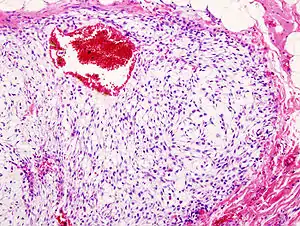

| Histopathologic image of chondrosarcoma of the chest wall. Surgical resection of recurrent mass. H & E stain. | |